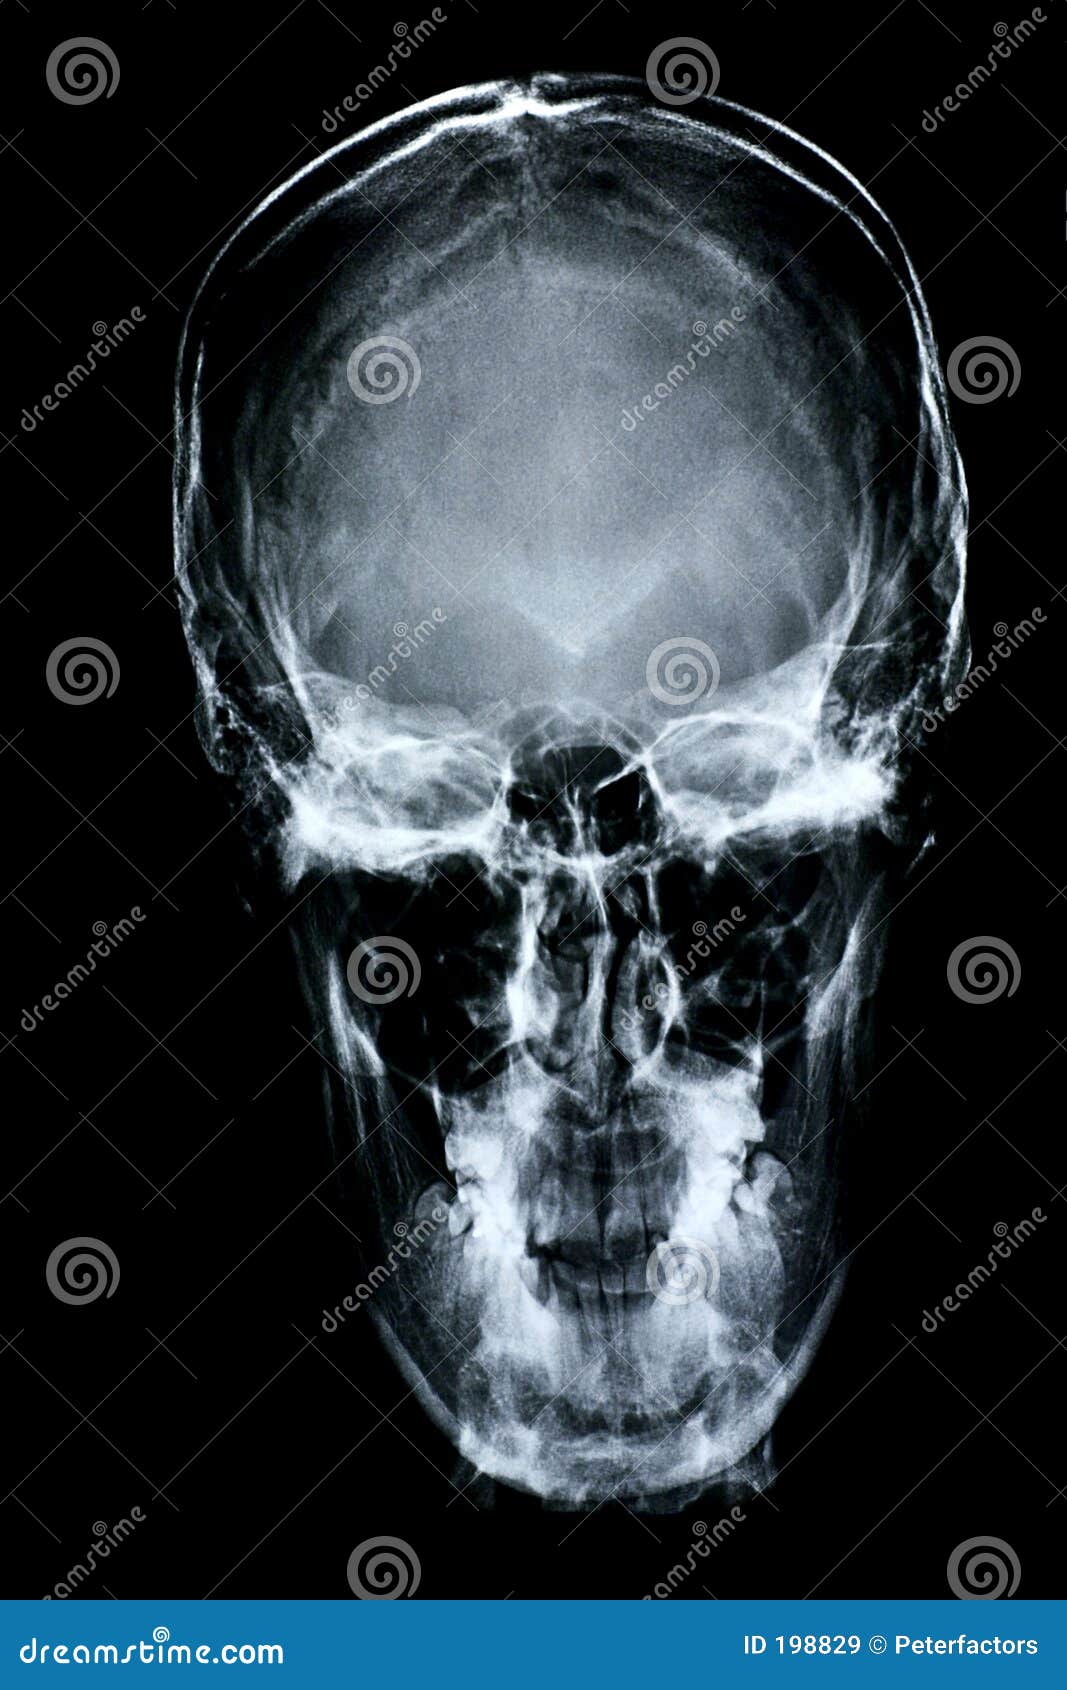

Parte Dianteira Do Raio X/face Foto De Stock - Imagem: 198830

pt.dreamstime.com

pt.dreamstime.com

raio dianteira xray raggi anteriore fronte opinião parti ossa

Parte Dianteira Do Raio X/face Imagens De Stock Royalty Free - Imagem

pt.dreamstime.com

pt.dreamstime.com

raio dianteira opinião xray